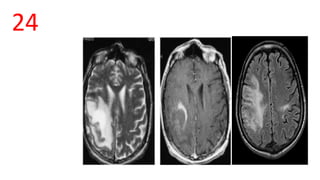

PML

• confluent, bilateral multifocal, asymmetric periventricular and

subcortical involvement and parietooccipital regions.

• invariably involves white matter, subcortical U-fibers

• T1: involved regions are usually hypointense

• T2: involved regions are hyperintense

• T1 C+ (Gd)

• typically there is no enhancement

25